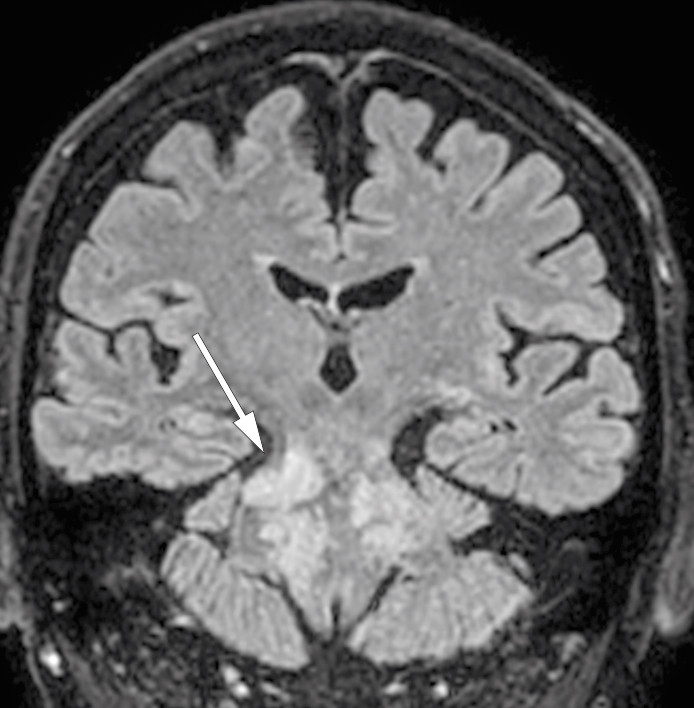

Pasienten ble gradvis bedre, og etter cirka en måned ble han dekanylert og overflyttet til nevrologisk avdeling. Ved utskrivelse etter 52 dager hadde han ingen dysartri, men lett redusert tempo og finmotorikk i høyre sides ekstremiteter og lett ataksi i underekstremitetene. Han var lett ustø ved gange. MR-kontroll tatt noen dager før utskrivelse viste tilbakegang av kontrastladende lesjoner (figur 3).

Ved kontroll ved nevrologisk poliklinikk fire måneder etter siste utskrivelse var pasienten orientert for person, tid, sted og situasjon. Han var i tydelig bedring og var ikke plaget med svimmelhet. Han hadde lette balansevansker, men klarte å gå lengre avstander. Kontroll-MR av hodet viste da ytterligere tilbakegang av kontrastladende lesjoner. Påfølgende kontroll-MR av hodet tatt ett år etter utskrivelse var uendret sammenlignet med forrige kontroll.

MR-funn er karakteristiske og spiller en avgjørende rolle i diagnostiseringen (3). Karakteristiske trekk er homogene, kontrastladende lesjoner større enn 3 mm i diameter, uten masseeffekt predominerende i hjernebroen og lillehjernen, med tydelig reduksjon av kontrastladning etter steroidbehandling. Lesjoner kan strekke seg til nærliggende sentralnervesystemstrukturer, kaudalt til den forlengede marg og ryggmargen, samt til supratentoriale regioner som talamus, capsula interna, basalgangliene, hjernebjelken og hvit substans (1, 3, 8).